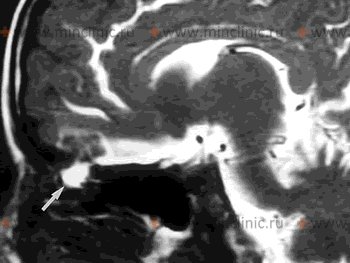

Источник назальной спонтанной ликвореи на МРТ головного мозга с контрастированием (показан белой стрелкой).

Реже дефект основания черепа находится в задней стенки лобной пазухи. Ещё реже ликворная фистула может располагаться в пирамиде височной кости. В этом случае спинномозговая жидкость (ликвор) попадает сначала в полость среднего уха, а потом через слуховую трубу в носоглотку и полость носа.